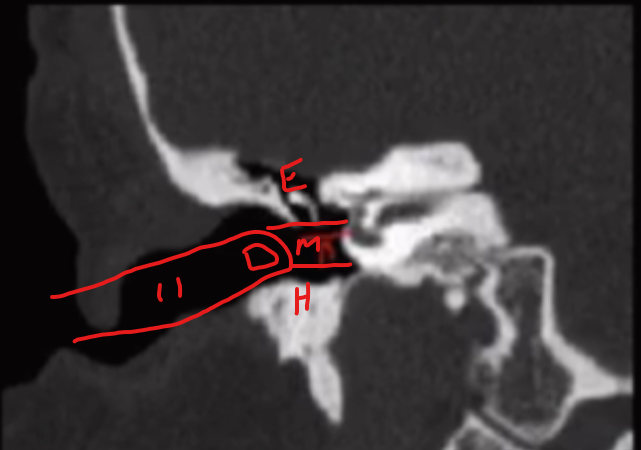

Tympanium

• Can described by using epi, meso and hypo -tympanum

• If you stick your finger in your ear

• Everything above = epitympanum

• Everything at level of finger = mesotympanum

• Everything below = hypotympanum

Prussak Space

• Clinical relevance - cholesteatoma arise here